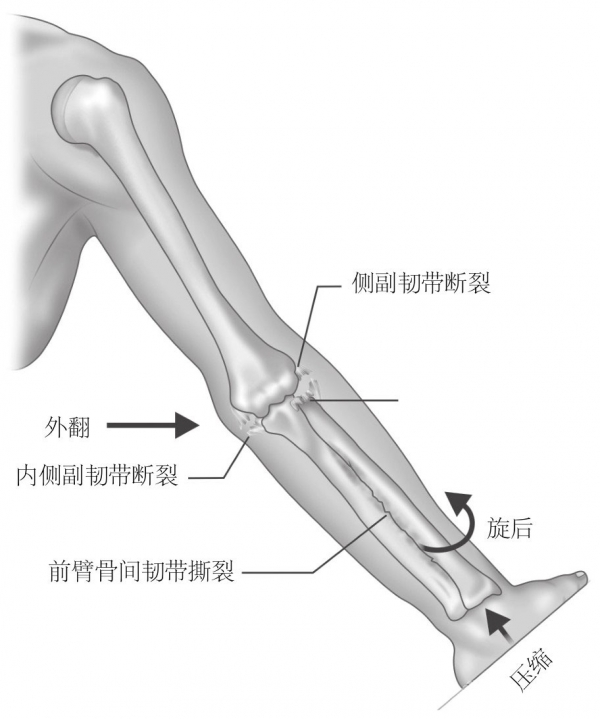

1. 了解患者的损伤机制。

该类损伤常见于高坠伤或高速运动下损伤,旋后位的轴向挤压及肘关节外翻应力致尺骨鹰嘴向后或后外侧移位,导致肘关节脱位(图1)。

图1 损伤机制